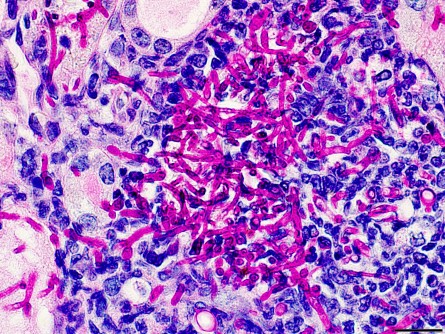

The fungus Candida albicans causes infections that range from superficial on the skin and nails to invasive into organs and the bloodstream. In recent decades, systemic candidiasis has increased due to more patients with immunosuppression from disease or treatments, prolonged antibiotic exposure and certain conditions such as kidney disease. Management of systemic candidiasis has become more difficult because of antifungal drug resistance, limited early diagnostic tools and absence of approved fungal vaccines.

Biswas and his coinvestigators used a murine model of candidiasis to look at neutrophils, which are the primary effector cells responsible for rapid fungal clearance during candidiasis. However, this natural antifungal activity depends largely on extracellular glucose, which becomes scarce in this infection process because C. albicans competes for the nutrient. What usually occurs is that metabolic competition within the host is a hostile environment that limits neutrophil survival and function, especially when underlying metabolic impairments (disease) are present.